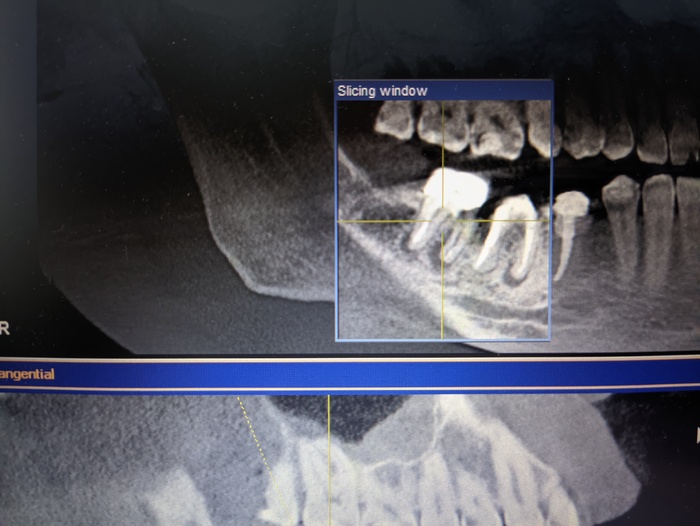

Весной 2021 лечил острый пульпит на 47 зубе, лечили каналы и депульпировали. Осенью поставил коронки на 45-47. В июле этого года сделал кт и врач сказал периодонтит и убыль кости на 46 и особенно на 47. Так понимаю 47 очень сложно вылечить будет. В клинике сказали, если не удастся вылечить, то только удалять. Имею ли я право по закону, если придется удалить 47 зуб, поставить в другой клинике имплант и потребовать с первой клиники компенсацию стоимости его установки ? Как правильно поступить?